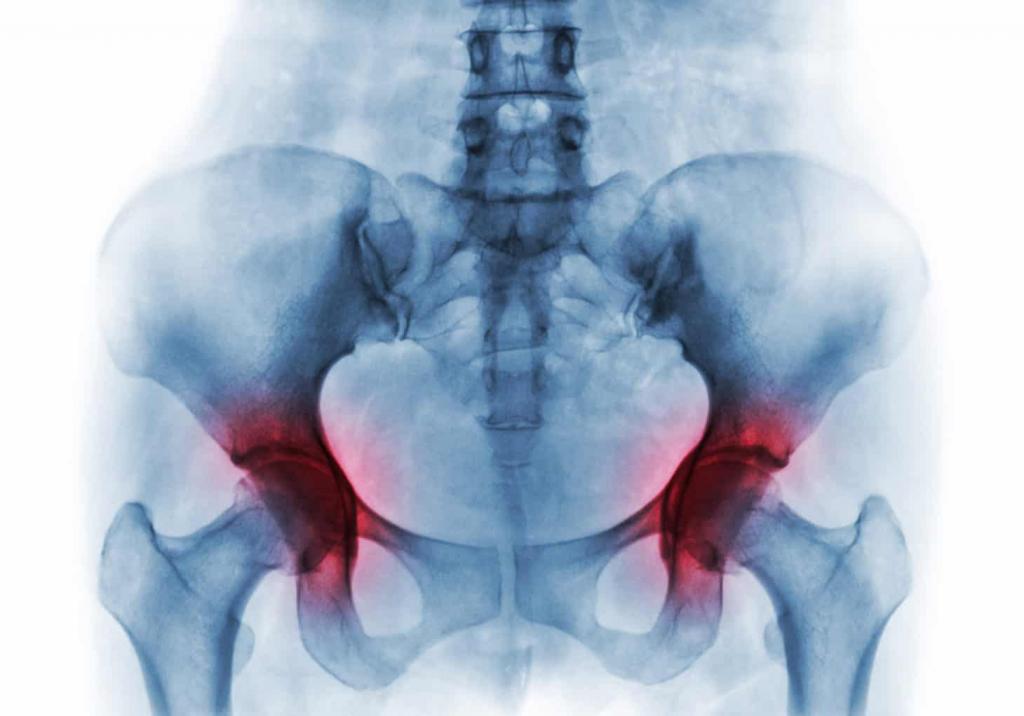

Здесь присуствует два вида парных сустава: крестцово-подвздошный и тазобедренный. Их деформация, воспаление или травма могут давать выраженный болевой синдром. В области таза располагается множество мышц и нервных волокон. Здесь же проходят важнейшие крупные кровеносные сосуды, отвечающие за иннервацию нижних конечностей. Патология любого из указанных отделов может спровоцировать боль.

- деформация и воспаление подвздошно-крестцового сочленения костей;

- деформирующий остеоартроз тазобедренного сустава;

- артрит, артроз или деформирующий остеоартроз тазобедренного сустава (для дифференциальной диагностики проводится функциональный тест, при котором пациенту предлагается сесть лицом к спинке стула с разведенными в разные стороны коленями);

- разрушение крестцово-подвздошного сустава (необходимо проведение рентгенографического обследования).